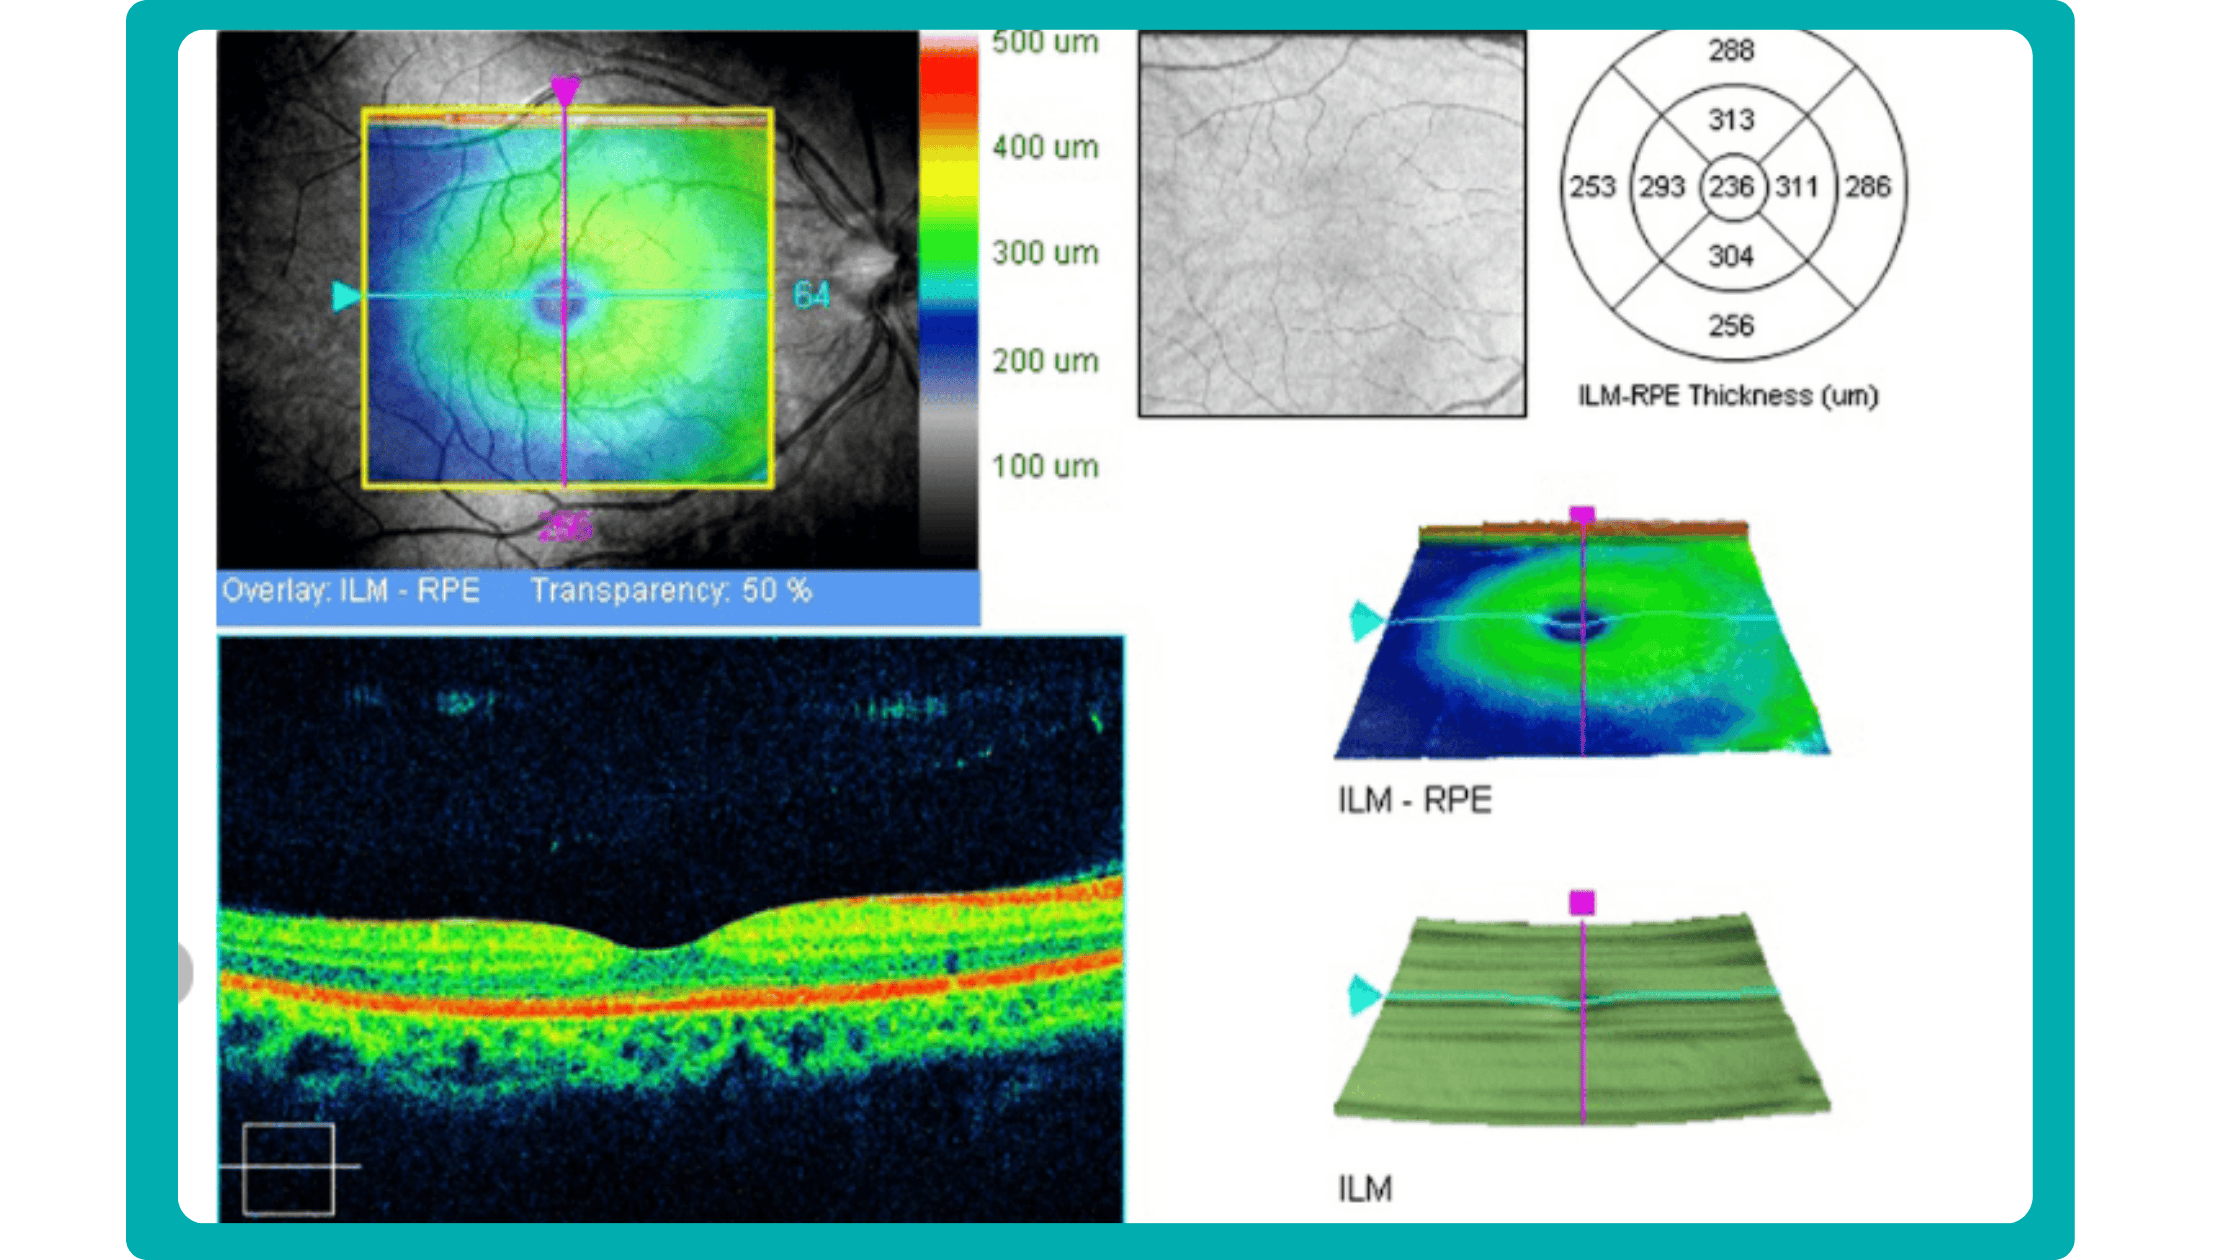

OCT report interpretation: 3 methods exist for displaying OCT data

Firstly, acquired 2D image slices are presented individually. This allows for detailed examination, but navigating through numerous images can be cumbersome, particularly with large datasets.

Secondly, a fundus image is displayed with superimposed retinal layers. This facilitates linking layers to the fundus, but only one layer can be examined at a time, hindering the analysis of multiple layers simultaneously.

Thirdly, the OCT tomogram is visualized in 3D, providing a comprehensive overview, but adjusting the visual representation often has limitations. Additionally, combined 3D visualizations of the tomogram and layers are typically unavailable, potentially obscuring spatial relationships.

Imaging biomarkers are a particularly attractive option for clinical practice due to their non-invasive and real-time nature. Quantitative measurements of retinal thickness, fluid volume, and other biomarkers relevant to diseases like diabetic retinopathy and age-related macular degeneration aid in treatment monitoring.

OCT reports with customized measurements and selected biomarkers, retinal layers, or segments allow for precise focus on treatment monitoring and patient response to therapy. This personalized approach enhances clinical decision-making by highlighting each case’s most relevant information.

In current clinical practice, macular damage assessment typically involves measuring the distance between the ILM and RPE layers, summarized in a post-scan report.

However, these reports often fall short of visualization best practices, employing ineffective or inconsistent color schemes. Additionally, they lack flexibility, with static visuals preventing in-depth examination of specific details. Despite these limitations, these reports remain valuable for many clinicians by distilling complex data into a manageable format.

Enhanced OCT data visualization offers a promising solution to these challenges. It enhances report clarity and comprehensibility while preserving the richness of the underlying data.

Subsequent follow-up visits will then display the most relevant picture, highlighting the most pertinent biomarkers for tracking a particular pathology (wet AMD in our example) and comparing their volume, progression, or regression through visits.

Another helpful option is retinal layer segmentation, which focuses solely on the retinal layers of interest for the specific case.

This level of customization empowers clinicians with a comprehensive yet targeted view of the patient’s condition. It saves time from manually detecting anomalies on scans and facilitates informed decision-making and personalized treatment plans.